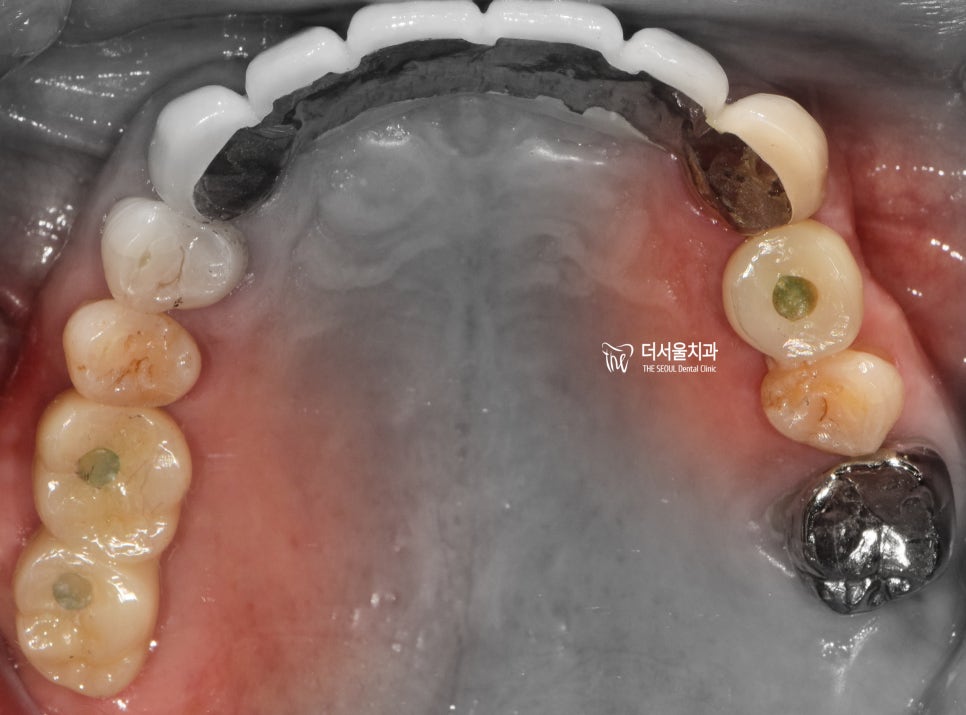

『c.c : 어금니가 없어요.』

상악에는 2곳에서 치아의 결손이 관찰되며

전체 엑스레이로 보게 되면 3곳에서

치아 결손이 관찰 됩니다.

지금 당장 식사를 하는것은 문제가 되지 않지만

이 상태를 그대로 유지를 하게 된다면

추후에는 더 큰 문제가 일어나기 쉬운 상태입니다.

치아 결손 부위에 따라서, 주위에 있는 치아들이

그 빈 틈을 메꾸려 이동을 하게 될 것이고

그에 따라서 결국 교합관계들이 무너지면서

식사를 하는것이 어렵게 되는 상황이

찾아올 수 있게 되는겁니다.